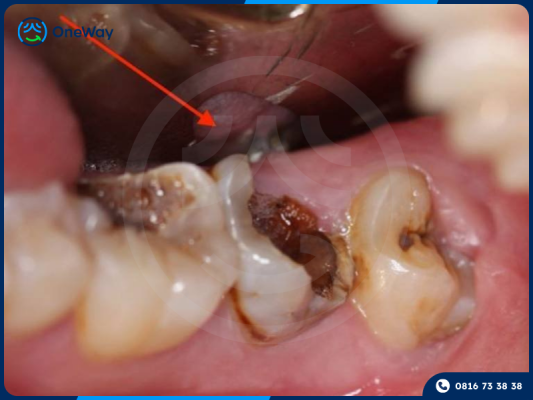

- Sâu răng quá nặng, mất gần hết thân răng, không còn mô răng đủ để phục hồi.

- Viêm tủy lan rộng, áp xe nặng, vi khuẩn có thể lây lan đến nướu, xương hàm, thậm chí ảnh hưởng đến sức khỏe toàn thân.

- Răng lung lay do tổn thương quá lớn không còn khả năng đứng vững trên cung hàm.